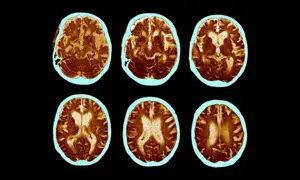

Novo Nordisk’s ‘lottery ticket’: can obesity drugs help treat Alzheimer’s?

Results are due soon from two studies using semaglutide to treat thousands of people with the disease